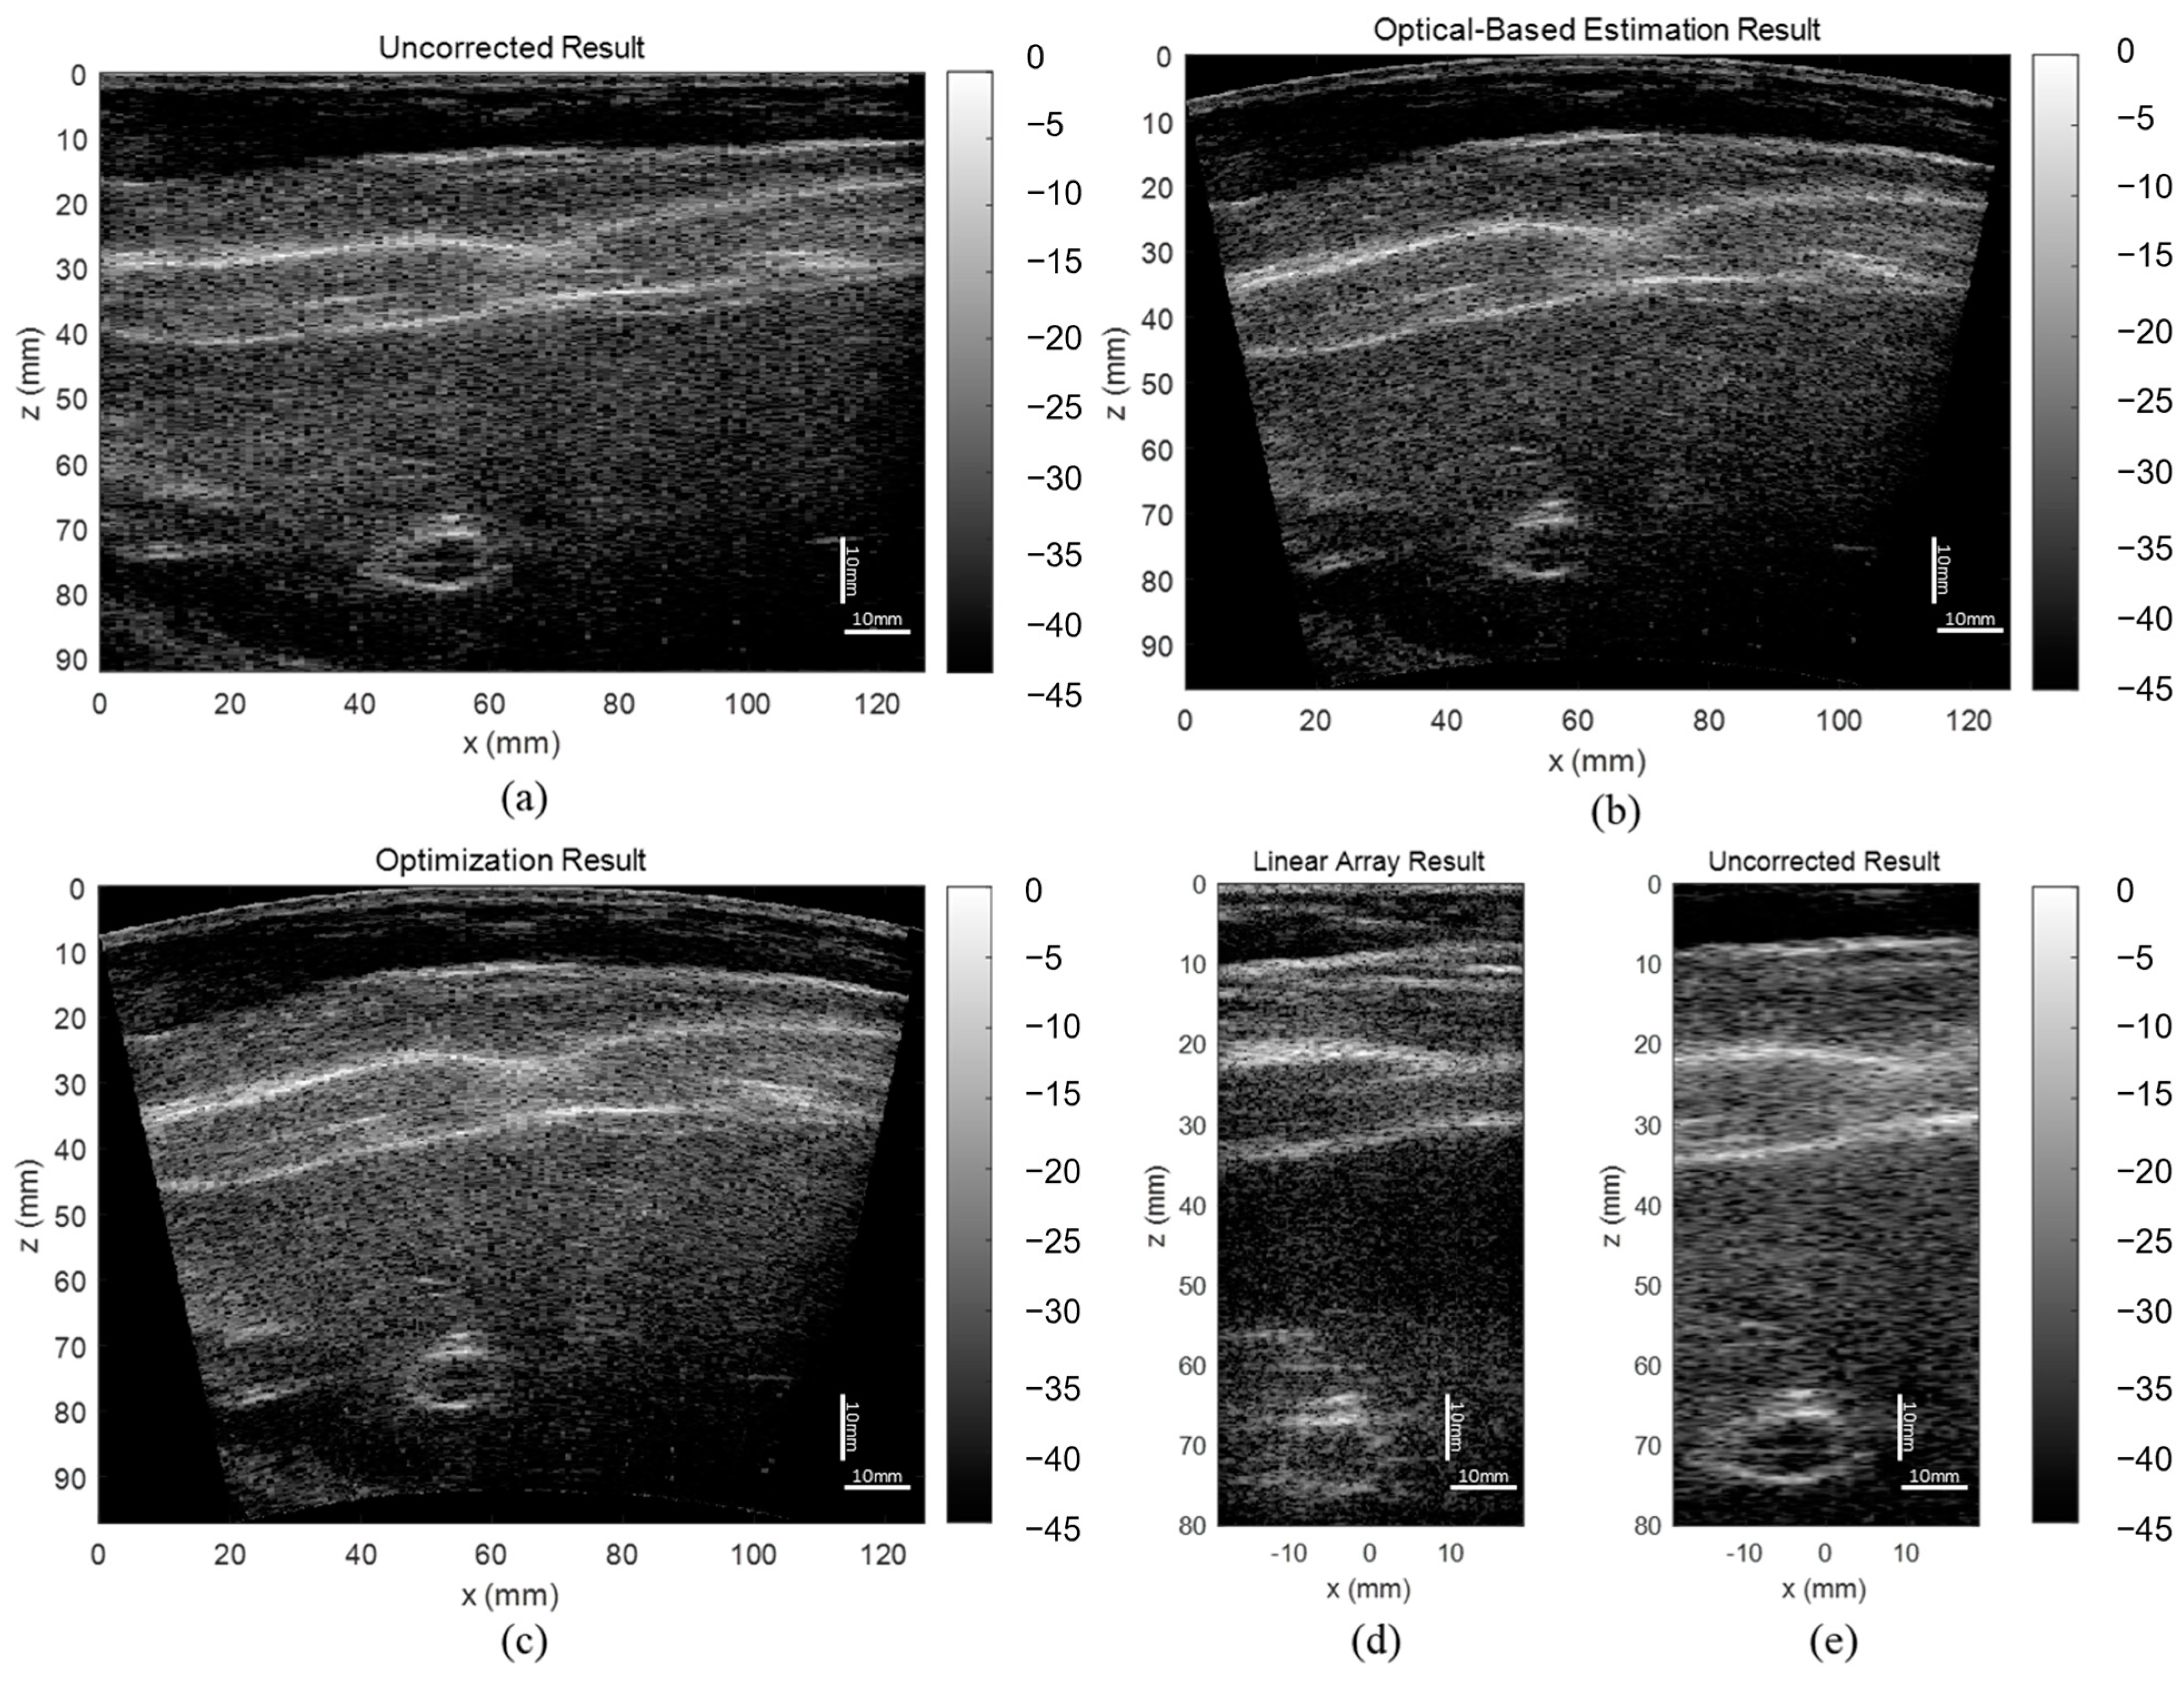

3.3. ABDFAN Phantom and Liver Scan Results

The uncorrected, optical-based estimation, and optimization results of the ABDFAN phantom and liver scan are shown in Figure 10 and Figure 11. The ground truth images from the linear array transducer are shown in Figure 10d and Figure 11d, and the same regions are cropped from the flexible array transducer results, and examples of the uncorrected results are depicted in Figure 10e and Figure 11e. The uncorrected results have significant distortions compared with the ground truth and corrected results. To quantitatively analyze the distortion, the cysts, blood vessels, and mussels are segmented as shown in Figure 12, and the Dice score, Jaccard index, and Hausdorff distance between the results and ground truth are evaluated and listed in Table 5, Table 6, and Table 7. The results show that both estimation and optimization algorithms can correct the distortions of the reconstructed image, and there is no significant difference between the two algorithms. The CNR and GCNR of the center cyst in the ABDFAN phantom and the large blood vessel in the liver scan are listed in Table 5, Table 6, and Table 7. In conclusion, the images reconstructed by both algorithms have an overall higher accuracy and contrast than the uncorrected images, and the optimization algorithm has a slightly better performance on estimating the array shape.

Figure 10.

Reconstructed images of the ABDFAN phantom (a) without array shape correction, (b) with optical-based estimated shape and (c) optimized shape, (d) ground truth image from the linear array transducer, and (e) cropped image with the same region as the ground truth.

Figure 11.

Reconstructed images of the liver scan (a) without array shape correction, (b) with optical-based estimated shape and (c) optimized shape, (d) ground truth image from the linear array transducer, and (e) cropped image with the same region as the ground truth.